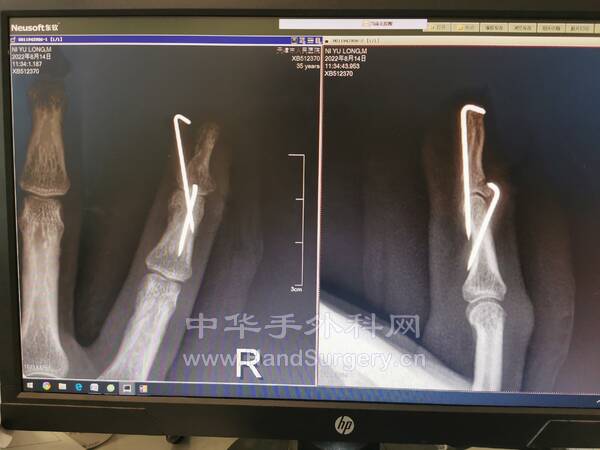

邢台的一名手外科医生的小指

受伤当时自己没有拍片

半个月后觉得不消肿,一直疼痛

在手术用C型臂拍了一下

才发现骨折了

试图复位不行